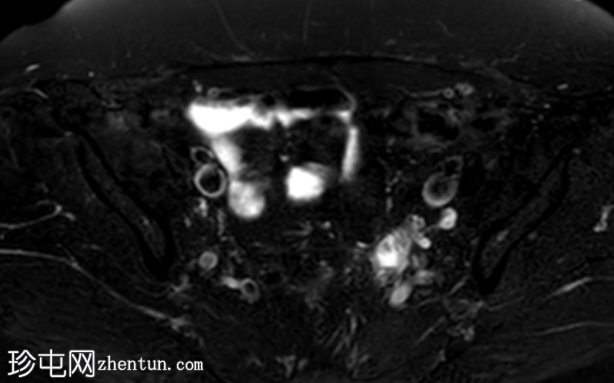

轴位T2加权像

脂肪抑制像

盆腔MRI显示左侧骶前区有两个小囊性病变,位于左侧附件的预期解剖位置。

病变在T2加权像上呈高信号,边界清晰,囊壁轻度增厚,光滑。在T1加权脂肪抑制像上,一个病变内部呈高信号,另一个病变呈低信号。静脉注射对比剂后,可见轻度周边囊壁强化,未见强化的实性成分。

未见扩散受限。病灶与邻近盆腔血管关系密切,无周围炎症改变、盆腔淋巴结肿大或游离液体的证据。